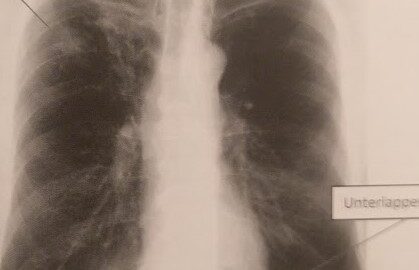

Diagnostik mit Röntgen

Bildgebende Diagnostik wie im Nativ-Röntgen oder auch im MRT sind mittlerweile möglich. Die Datensammlung diesbezüglich ist vorhanden und Thorax und Lungenbefall Vergleiche können gemacht werden. Aber man sollte die Diagnose im Gesamtkontext zusammenführen und nicht nur aufs Röntgen verlassen.

Bei konventionellen Röntgen sind auch unauffällige Befunde möglich. Die Chance steht bei ca. fifty-fifty. Der häufigste Befund sind die sogenannte Infiltrate (siehe Titelbild). Ein ähnliches Bild wie bei einer Tuberkulose. Es müssen nicht zwangläufig beide Lungen befallen sein.